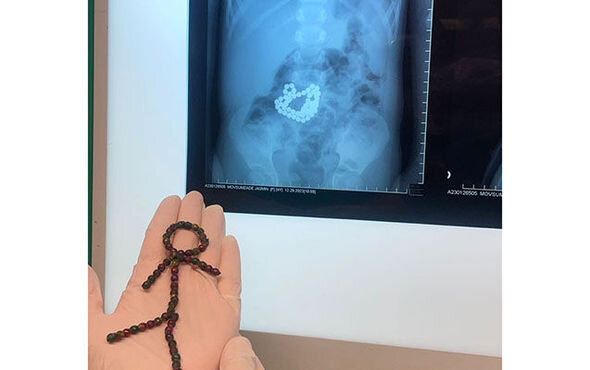

Bakıda azyaşlı uşaq 53 maqnit udub - FOTO

Bakıda dörd yaşlı uşaq 53 ədəd maqnit oyuncaq udub.

Azyaşlı düz bir ay bağırsağında həmin oyuncaqlarla yaşayıb.

Maqnitlər uşağın həyatını riskə atdığından, o, əməliyyat olunub.

Hazırda uşağın vəziyyətinin yaxşı olduğu bildirilir.